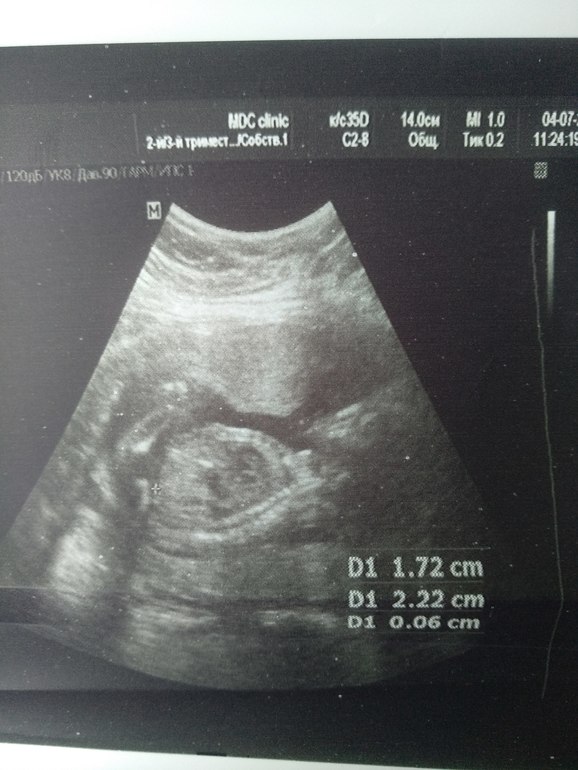

Врачь сказала мальчик , но я что то ни одного фото не увидела где точно мальчик , и не верится мне , мне кажется она ошиблась , результат НИИП уже жду месяц, мой гинеколог ушла в отпуск , вот скоро второй скрининг еще там спрошу, просто хотела что б вы все посмотрели, не одна я ничего не вижу , хотя доктор говорит я вам везде плюсики поставлю где смотреть , ну что то беленькое и все , вот что я вижу.

Где плюсик стоит, там видно «кофейное зернышко» -это на девочку указывает... мне вот на втором скрининге Доктор сказал «девочка», хотя я нипт делала, и уже в 11 недель знала, что будет здоровый мальчик))) Желаю вам мальчика, А главное ,пусть пусть будет здоровый малыш!!!

Приветик знатоки!!! Знаю что рано но погадайте мне кого же мы ждём? Пол ребёнка _ предчуствие...